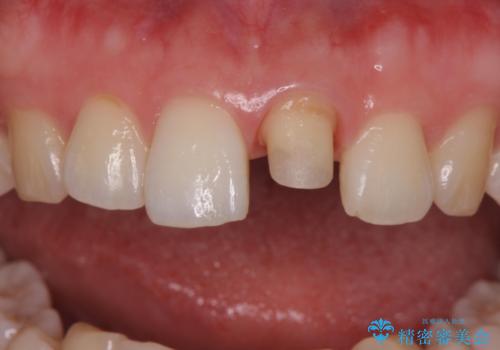

- 前歯の変色とガタつきが気になるとのことで来院された患者様です。

根管治療からやり直しを行った後、ジルコニアクラウンで修復することで、ガタつきと変色の両方を改善していきます。